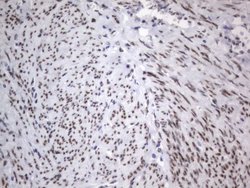

| Immunohistochemistry (Paraffin), Western Blot | |